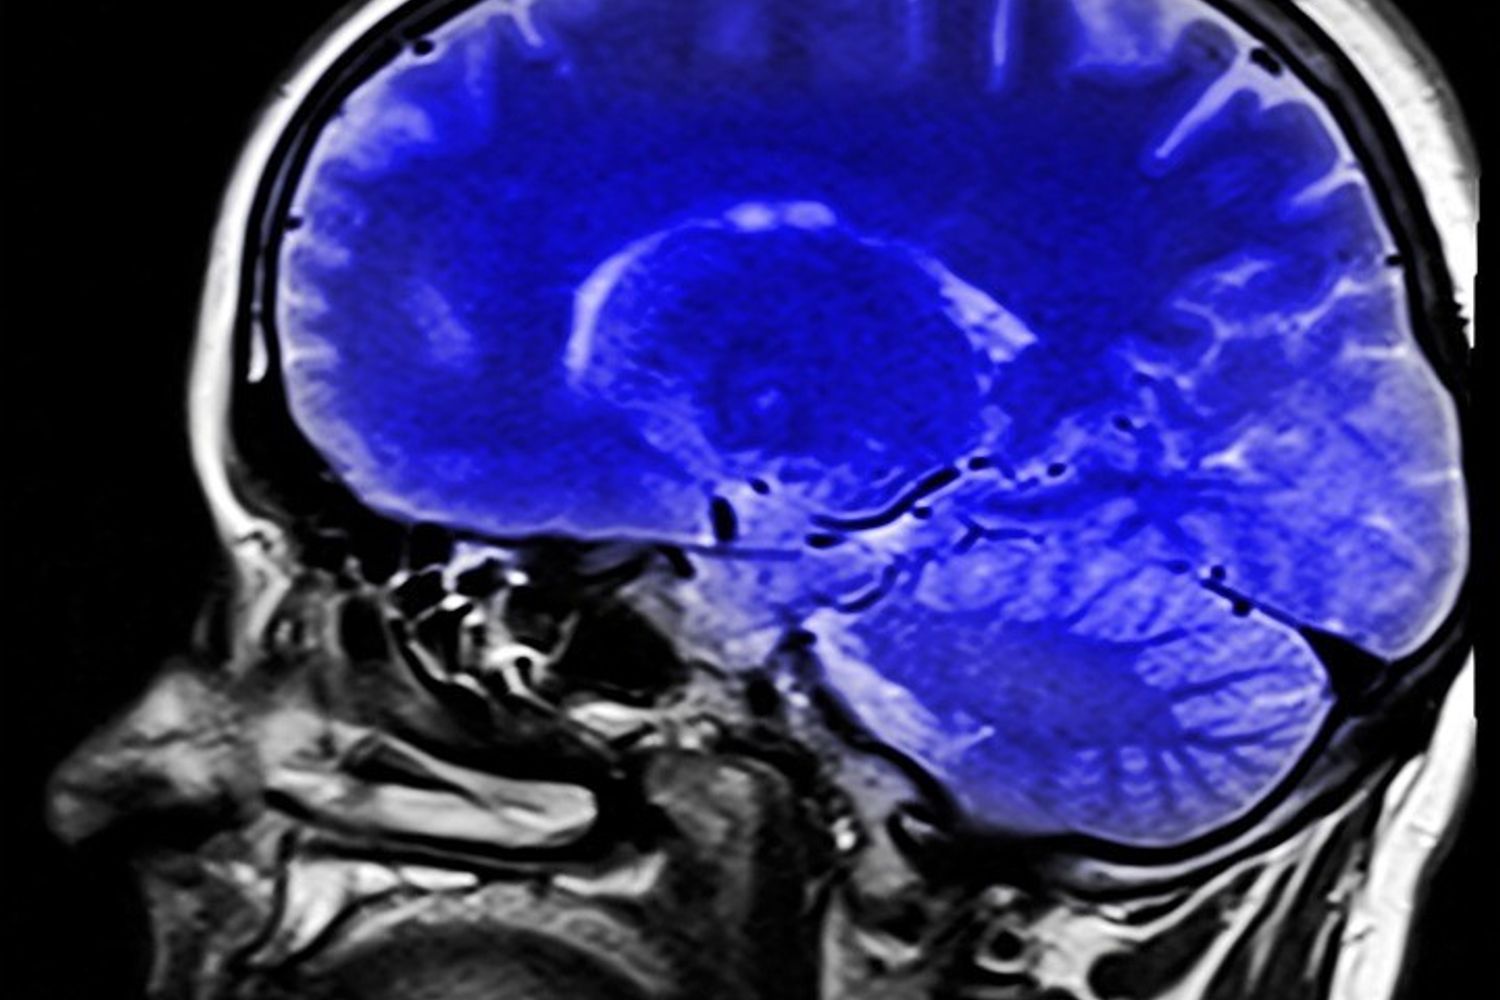

AGI - La dipendenza da internet negli adolescenti sembra associata a delle interruzioni nelle regioni del cervello coinvolte in più reti neurali. Lo dimostra uno studio, pubblicato sulla rivista Plos Mental Health, condotto dagli scienziati dell'University College di Londra. Il team, guidato da Max Chang e Irene Lee, ha esaminato i dati di neuroimaging sugli effetti della dipendenza da internet tra i ragazzi adolescenti. Le informazioni provenivano da 12 ricerche precedenti, condotte su ragazzi con dipendenza da internet. I lavori considerati, che soddisfacevano i criteri dei ricercatori, erano stati condotti tutti in Asia. Le reti neurali, spiegano gli esperti, svolgono un ruolo centrale nel controllo dell'attenzione, nell'abilità intellettuale, nella memoria di lavoro, nella coordinazione fisica e nell'elaborazione emotiva.

Stando a quanto emerge dall'indagine, quando gli adolescenti con dipendenza da Internet erano impegnati in attività governate dalla rete di controllo esecutivo del cervello, come comportamenti che richiedono attenzione, pianificazione, processo decisionale, le aree cerebrali mostravano una significativa interruzione nella loro capacità di lavorare insieme rispetto a quanto osservato in individui della stessa età senza dipendenza. Queste alterazioni suggeriscono che alcuni comportamenti, legati anche all'auto-introspezione e all'attenzione, possono risultare più complicati da eseguire.